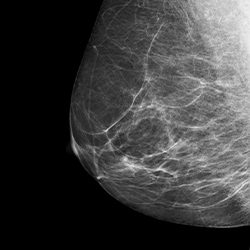

대학병원급 초음파 장비

캐논 Aplio i700 초음파

균일한 이미지와 영상을 제공하여

정밀 진단이 가능

• 유방암, 섬유선종, 유선증, 물혹, 농양 등

• 탄성초음파 기능 완비 / 미세석회화 검사

한국 여성에게서 나타나는 치밀유방 진단을 위한